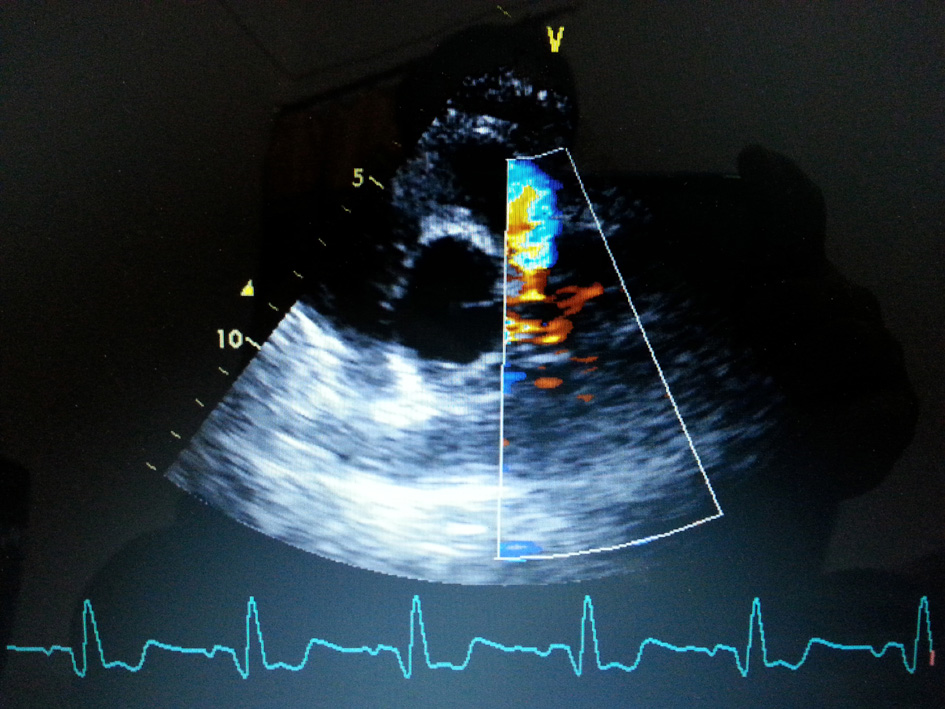

A 75-year-old woman presented with exertional angina that had progressed during previous 6 months to Canadian Cardiovascular Society functional class II at the time of admission to the hospital. Her pulse rate was 74 beat per minute and blood pressure was 152/94 mm Hg in right arm in supine position. There was no family history suggestive of coronary artery disease. Physical examination was unremarkable. On auscultation, pansystolic murmur (Levine 3/6) more prominent at the apex with radiation to axilla was heard. Mild cardiomegaly with enlargement of left ventricle and left atrium was noted on chest roentgenogram films. Electrocardiogram displayed poor R progression in precordial leads and ST-segment depression in leads V5-6, suggesting left ventricular hypertrophy. Trans-thoracic echocardiogram and color-Doppler established presence of continous flow entering the pulmonary trunk, mild mitral leak and normal systolic function (Fig. 1). Because of mild osteoarthritis of both knees, tread mill test could not be done. After proper consent, patient was taken to catheterization lab. Coronary cine-angiogram showed dilated and tortuous RCA with absence of a left coronary ostium in the left aortic sinus (Fig. 2). During the delayed phase, abundant intercoronary anastomoses (Rentrop grade 3 intercoronary collateral) were communicating with left coronary artery (Fig. 3) and still very delayed in filming sequence, retrograde flow from the left anterior descending and left circumflex coronary arteries was opacifying the left main coronary artery and its origin from the main pulmonary artery thus establishing diagnosis of ALCAPA (Fig. 4). Similar finding was recognized on reconstructed 3D coronary CT angiogram thus confirming ALCAPA (Fig. 5). Though surgical treatment by recreating a dual coronary perfusion is usually warranted regardless of the symptoms or myocardial function, it was decided not to intervene surgically as risk of cardiac surgery was outweighing the benefit. She was discharged in stable condition with medical management.

|  Click for large image | Figure 1. Transthoracic echo-parasternal short-axis view showing presence of continuous flow entering the pulmonary trunk. |